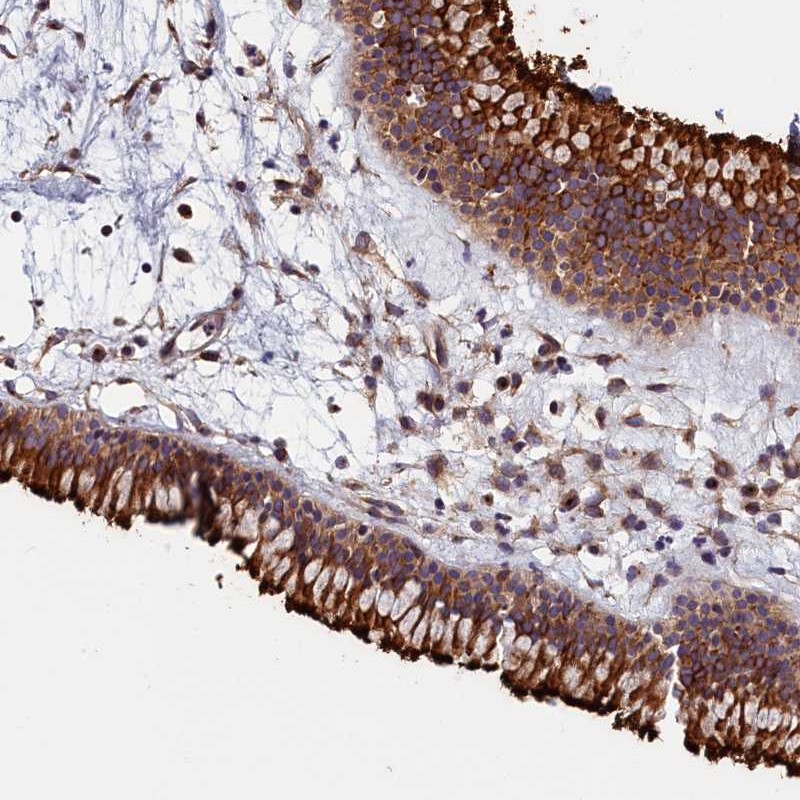

Immunohistochemical staining of human nasopharynx shows strong cytoplasmic and membranous positivity in respiratory epithelial cells.